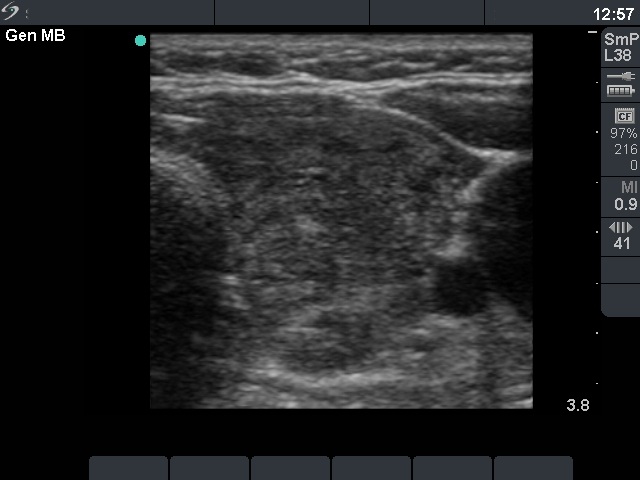

Ultrasonography: the thyroid was hypoechogenic with two well-circumscribed hyperechogenic areas in the right lobe. These were surrounded with a halo and presented perinodular blood flow.

Comment: it was unequivocal that the patient had Hashimoto's thyroiditis. The sonographic picture was equivocal whether the patient had nodule or nodules, too. However, the cytology was more problematic. It became evident after histopathology that the lesion in question was a focus with proliferation of oxyphilic cells. What did we do wrong? I think that such cytological picture itself is almost identical with that seen in a Hürthle-cell tumor. Although there were signs which disfavor the possibility of tumor, we could not exclude the presence of tumor with enough safety. Two minor signs were remarkable: firstly, the presence of nuclear debris which was suspicious for the presence of lymphocytic infiltration even within this lesion ; secondly, the lack of prominent nucleoli decreased the possibility of a Hürthle-cell tumor. The US appearance of the 'nodules' were remarkable. In contrast with a real nodule, these were irregular. Circumscribed areas were also found in the left lobe. Moreover, a follicular tumor is solitary in most cases.